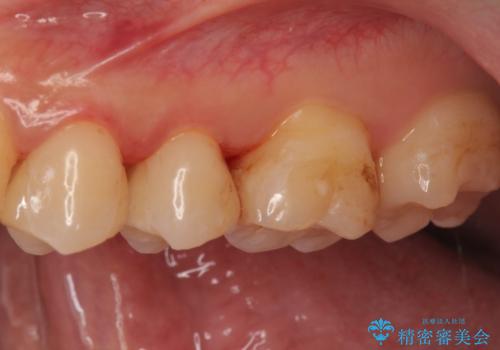

セラミックの詰め物(e-maxインレー)にて治療を行いました。

- e-maxインレー 7.7万円 ×2本費用は治療当時の料金となります

セラミックの詰め物(e-maxインレー)は、歯と詰め物の隙間がなく

虫歯の再発リスクを下げる事ができます。